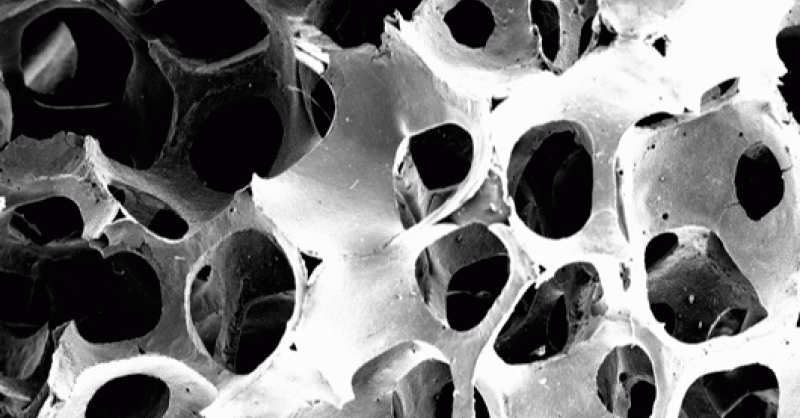

Partículas de colágeno

Estos investigadores ha conseguido incorporar, por primera vez esta sustancia, conocida por sus propiedades elásticas en la piel, a los agentes encargados de la formación y composición del hueso, HA (estructura del hueso) y BTCP (formador del hueso), lo cual supone una revolución en la regeneración y aumento de densidad de la estructura ósea.

Los resultados de incorporar esta proteína a las células óseas creadas en el laboratorio (biomaterial) se traduce en una cicatrización más rápida y una mejora significativa en la recuperación de intervenciones odontológicas, principalmente, en pacientes que presentan signos de osteoporosis